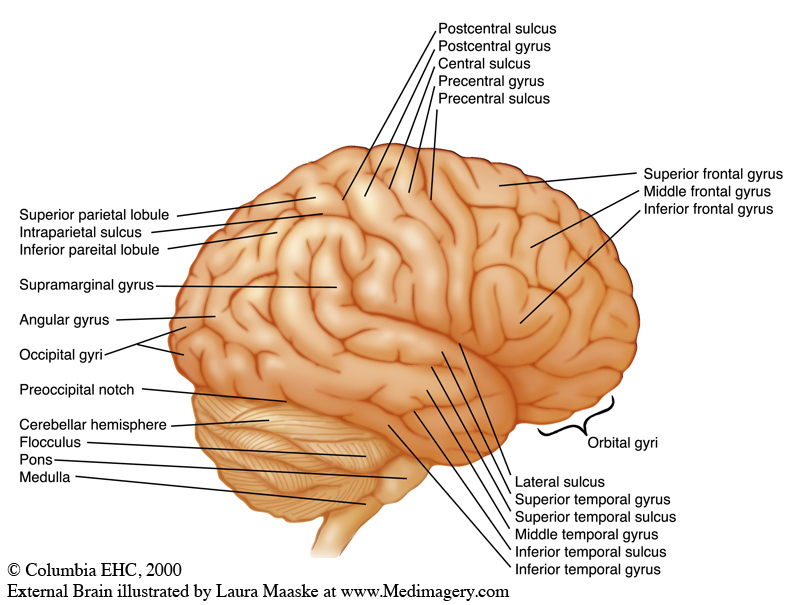

Супрамаргинальная извилина: Функции и Исследования